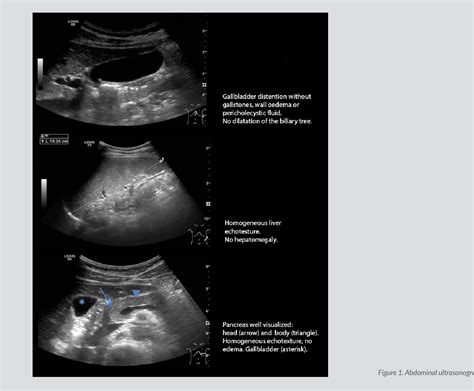

• Imaging Studies: Ultrasound, computed tomography (CT) scan, or magnetic resonance imaging (MRI) may be used to visualize the liver and surrounding structures. These imaging studies can help identify inflammation or other abnormalities.